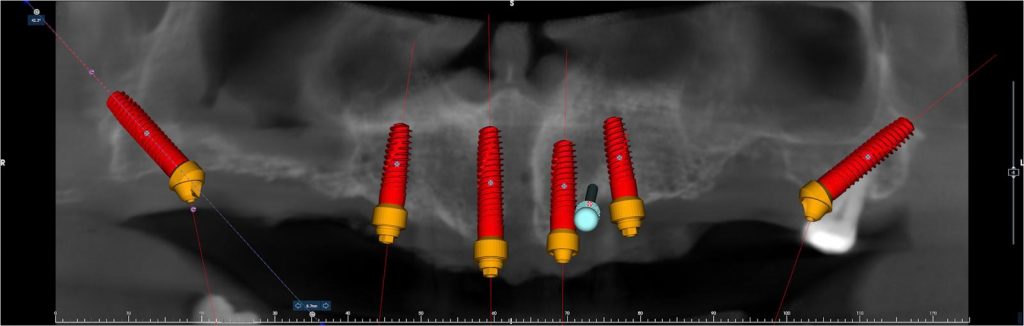

El tratamiento con implantes pterigoideos comienza con una fase de diagnóstico exhaustivo. Se realiza un estudio clínico y un TAC 3D (CBCT) para analizar la anatomía del maxilar, la calidad ósea y la relación con estructuras anatómicas cercanas.

Tras el estudio radiológico, se lleva a cabo una planificación digital personalizada, donde se define la posición, longitud y angulación de los implantes. La colocación de los implantes pterigoideos requiere una técnica quirúrgica precisa debido a la profundidad y localización del hueso pterigoideo.

Las imágenes clínicas y radiográficas permiten observar la posición y angulación característica de los implantes pterigoideos, así como su integración en rehabilitaciones completas del maxilar superior.